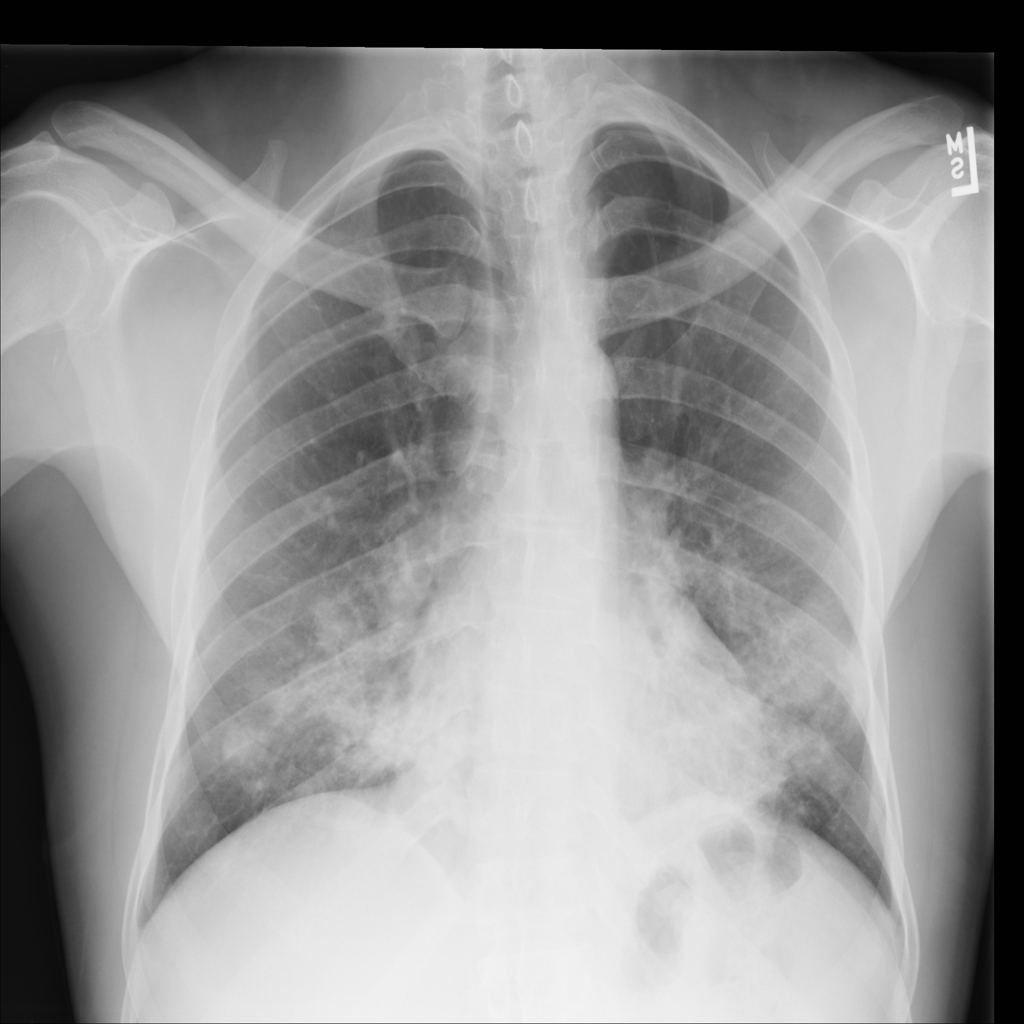

PAT-A1E2 · IMG-001Pneumonia

PAT-A1E2 · IMG-001

AP